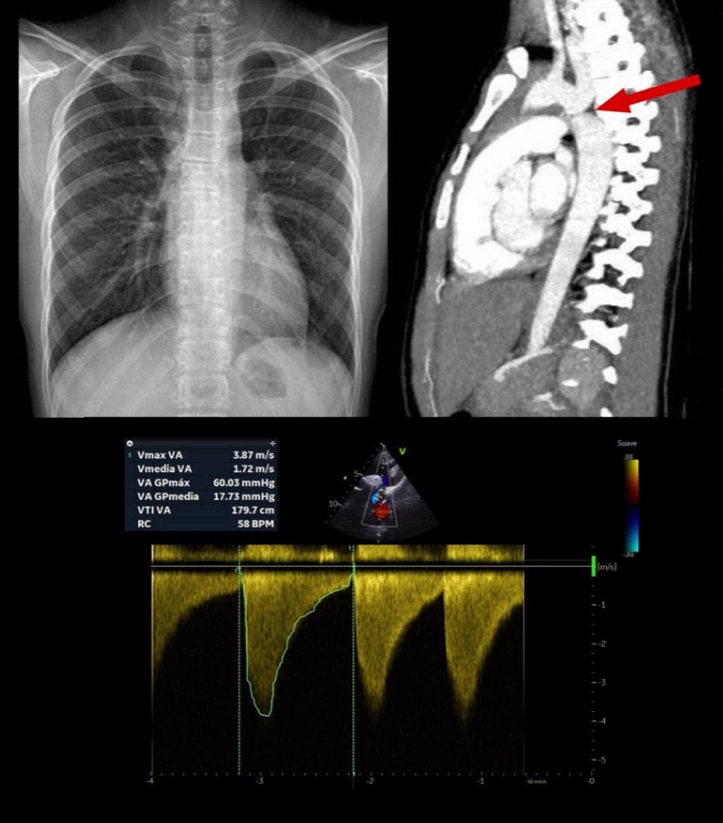

Paciente mujer de 12 años que acude a consulta de su centro de salud por inapetencia. Valorada hace 5 meses por cefalea, con cifras de TA sistólica de 110 mmHg (percentil [P] 67, 0,40 desviaciones estándar [DE]) y diastólica de 60 mmHg (P42, -0,21 DE). Consultó en el Servicio de Urgencias externo por episodio de gastroenteritis aguda, donde se registran cifras de TA sistólica de 130 mmHg (>P99, 2,36 DE) y diastólica de 90 mmHg (>P99, 2,53 DE). Ante la evidencia de estas cifras se realiza exploración física, en la que destacan pulsos femorales débiles y se repite medición de TA, realizándose tomas en decúbito, bipedestación y sedestación, con cifras de HTA en todas ellas. Se determina la TA en miembros superiores derecho e izquierdo, con 136/76 y 156/82 mmHg, respectivamente, y en miembros inferiores derecho e izquierdo, con cifras de 84/63 y 92/69 mmHg. Se realiza electrocardiograma (ECG) y radiografía torácica, sin hallazgos significativos. Es derivada a Cardiología Pediátrica, con sospecha de coartación de aorta. La ecocardiografía evidencia una reducción significativa del calibre de istmo aórtico con gradiente de hasta 60 mmHg y latido prolongado en aorta abdominal, confirmándose la sospecha de coartación. Se realiza angioTAC para medida de zona de coartación previa a realización de cateterismo terapéutico con implante de stent (Figura 1).

Figura 1. Pruebas complementarias